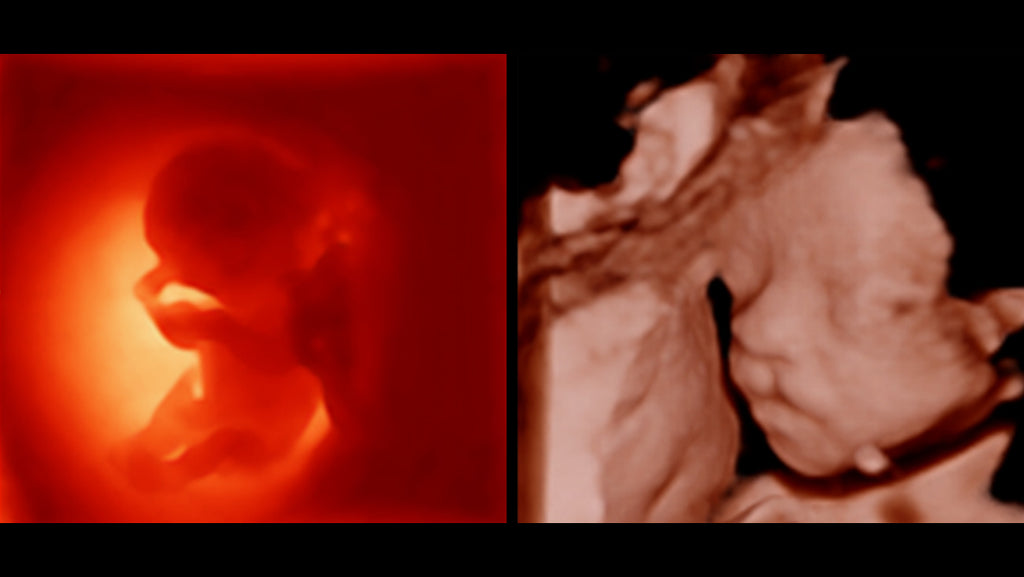

Como una solución de obstetricia, ginecología e imagen general completa, proporciona una interfaz muy robusta e intuitiva. Supera las expectativas de tus rastreos con su sistema de transductores pure crystal